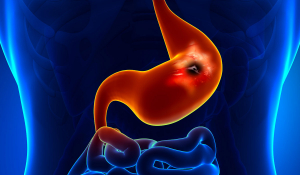

Ускладнення виразкової хвороби шлунку: причини та лікування у Івано-Франківську.

Виразкова хвороба шлунку є однією з найбільш поширених проблем травного тракту, яка впливає на тисячі людей по всьому світу. Попри наукові досягнення в медицині, ускладнення виразкової хвороби можуть бути серйозними і вимагати негайного медичного втручання. У даній статті ми розглянемо причини, симптоми та методи

лікування ускладнень виразкової хвороби шлунку.